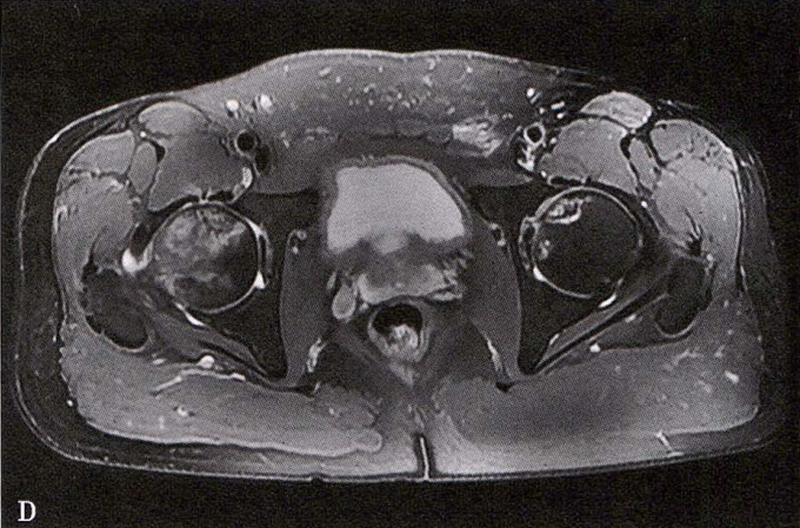

A.男性,71岁,双侧股骨头坏死,右侧Ⅰ期、左侧Ⅲ期。X线片示双侧股骨头形态可,右股骨头未见明显密度改变,左股骨头关节面下见局限性骨密度减低及增高区(A1)。MRI(T2加权像)示右股骨头内双线征,左侧不规则形混杂信号,坏死区远端骨髓水肿(A2、A3)。